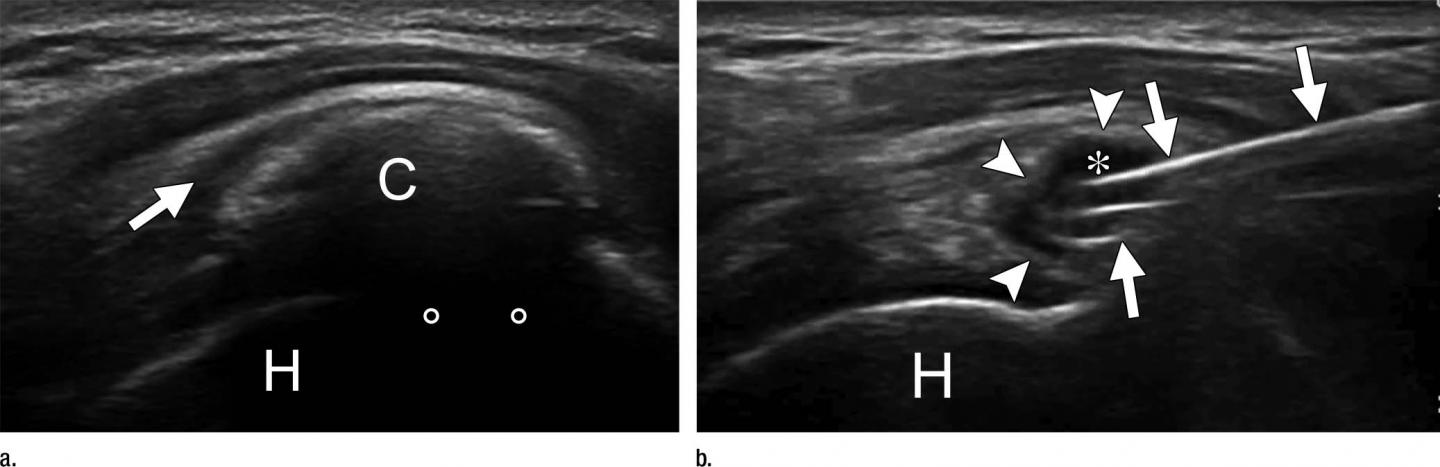

Ultrasound exams were performed on each patient to identify the exact location of calcium deposits in the tendons and whether the deposit appeared to be hard or fluid. For patients in the double-needle procedure group, 16-gauge needles were inserted inside the calcification under continuous ultrasound monitoring, and the area was flushed with injections and extractions of saline until the tendon was free of visible calcium. The single-needle procedure utilized an 18-gauge needle for the injection and extraction.